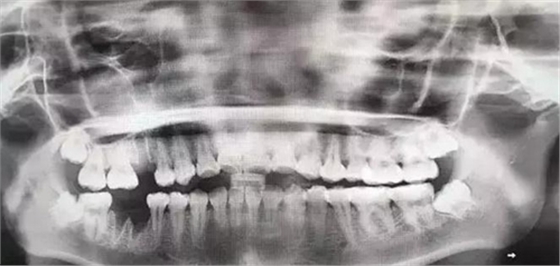

由于智齒的生長位置特殊,導致了拔除難易不同,如智齒出現(xiàn)橫著長或者靠近牙神經(jīng)的話,則難度會較高,一般人只需拍個口腔全景片,但相對于智齒靠近神經(jīng)管的情況,還可能需要拍CT,這都很考驗牙醫(yī)的技術(shù)。

下面這兩張圖,據(jù)說拔牙費時1.5小時,收費14000元。